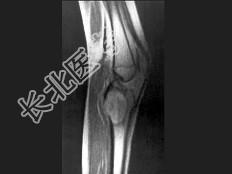

- 单项选择题女,13岁, 右膝部痛,结合图像, 最可能的诊断是 ( )

A、胫骨近端动脉瘤样骨囊肿

B、胫骨近端成软骨细胞瘤

C、胫骨近端骨巨细胞瘤

D、胫骨近端内生软骨瘤

E、以上都不是